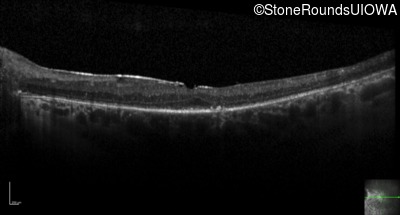

Optical Coherence Tomography - Left - 20/30 +2

Exemplar / OCT Stack

OCT Stack